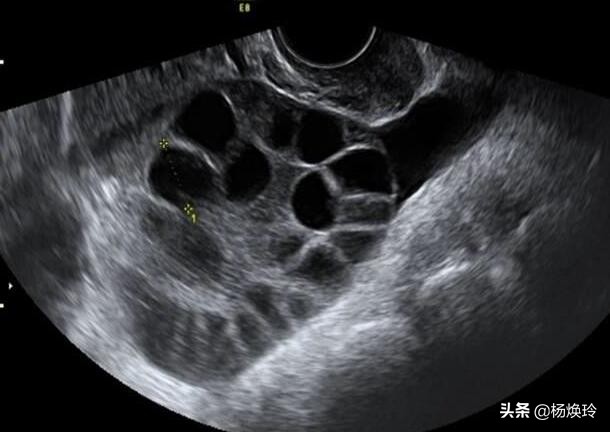

事后,我为她讲解卵巢过度刺激综合 征,这种病为体外受孕辅助生育的主要并发症之一,是一种人体对促排卵药物产生的过度反应,以双侧卵巢多个卵泡发育、卵巢增大、毛细血管通透性异常、异常体液和蛋白外渗进入人体第三间隙为特征而引起的一系列临床症状的并发症。会 引起患者胸腹水,尿少,血液浓缩,电解质紊乱,肝肾功能受损的变化,威胁患者生命。小刘苦恼不已,难道就不能要孩子了?